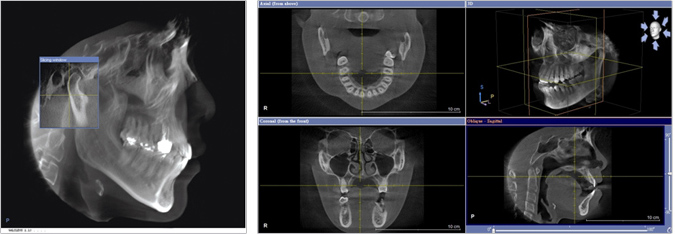

CT電腦斷層,可旋轉360度,瞭解口腔全貌,維護閣下的手術安全